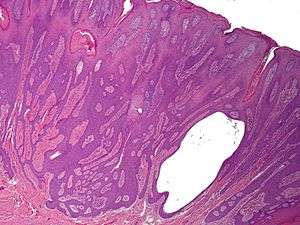

Syringofibroadenoma (also known as "Acrosyringeal nevus of Weedon and Lewis") is a cutaneous condition characterized by a hyperkeratotic nodule or plaque involving the extremities.[1]:668

It is considered of eccrine origin.[2]